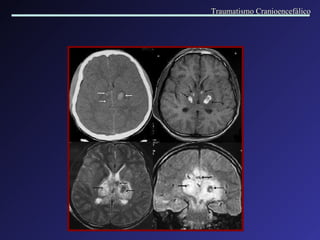

Traumatismo Cranioencefálico

Contusões múltiplas e hematomas intracerebrais Densidade mista: múltiplas áreas de hemorragia com edema perilesional. Traumatismo Cranioencefálico

Hematoma intracerebral  Contusão hemorrágica multifocal Múltiplos pequenos focos hemorrágicos localizados em torno de vasos sanguíneos, no espaço de Virchow- Robin. Traumatismo Cranioencefálico